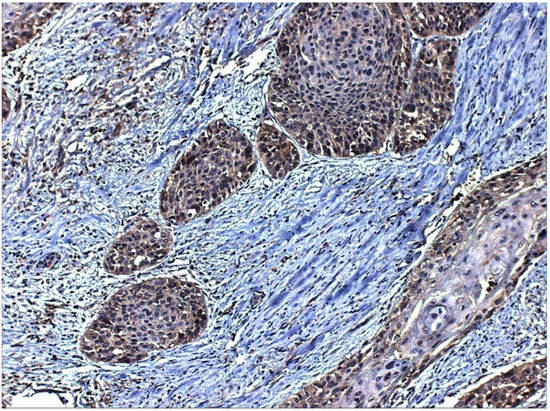

- Esteban, F.; Gonzalez-Moles, M.A.; Castro, D.; Martin-Jaen, M.d.M.; Redondo, M.; Ruiz-Avila, I.; Muñoz, M. Expression of substance P and neurokinin-1-receptor in laryngeal cancer: Linking chronic inflammation to cancer promotion and progression. Histopathology 2009, 54, 258–260. [Google Scholar] [CrossRef] [PubMed]

- Brener, S.; González-Moles, M.A.; Tostes, D.; Esteban, F.; Gil-Montoya, J.A.; Ruiz-Avila, I.; Bravo, M.; Muñoz, M. A role for the substance P/NK-1 receptor complex in cell proliferation in oral squamous cell carcinoma. Anticancer Res. 2009, 29, 2323–2329. [Google Scholar]